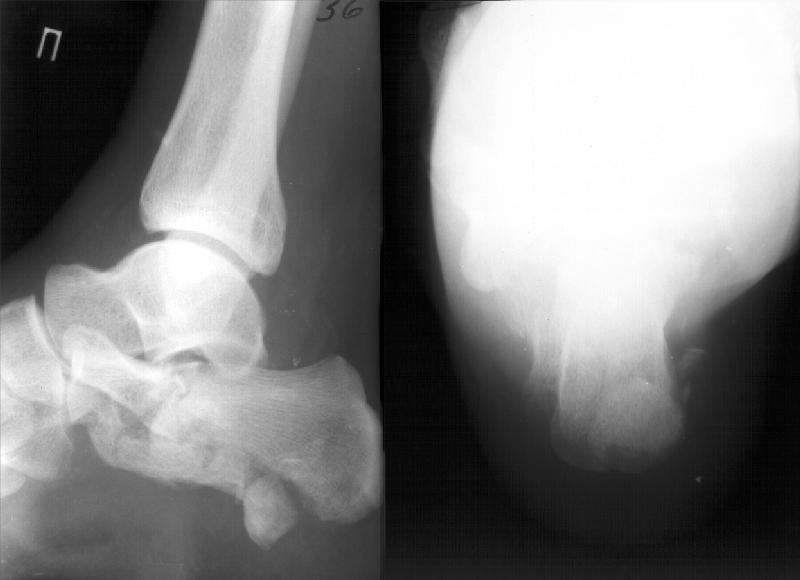

Данный перелом можно классифицировать как "языкообразный" (по Essex-Lopresti), но имеется еще раздробление переднего отдела пяточной кости.

Как метод выбора, по мнению нашей клиники, является закрытая аксиальная репозиция аксиальная фиксация "языкообразного" фрагмента винтом Шанца под контролем ЭОПа. Технически это возможно в сроки до 10 дней, важно правильно

На этой неделе оперировали. КТ наши рентгенологи сделали зачем-то горизонтальной плоскости, поэтому не привожу. Сделали открытую репозицию, заполнили дефект трансплантатом из крыла подвздошной кости.

После удаления спиц положение фасетки немножко ухудшилось. Такие дела. Жду комментариев.

Судя по вашим рентгенограммам, восстановить суставную поверхность таранно-пяточного и пяточно-кубовидного сустава полностью не удалось, хотя угол Белера выглядит гораздо лучше, чем на предоперационной рентгенограмме,

В данном случае восстановлена лишь ось пятки - угол Белера в боковой проекции и смещение кнаружи и по длине в прямой. Гораздо проще и с несравнимо меньшим риском этого можно остигнуть, применив внешний остеосинтез.